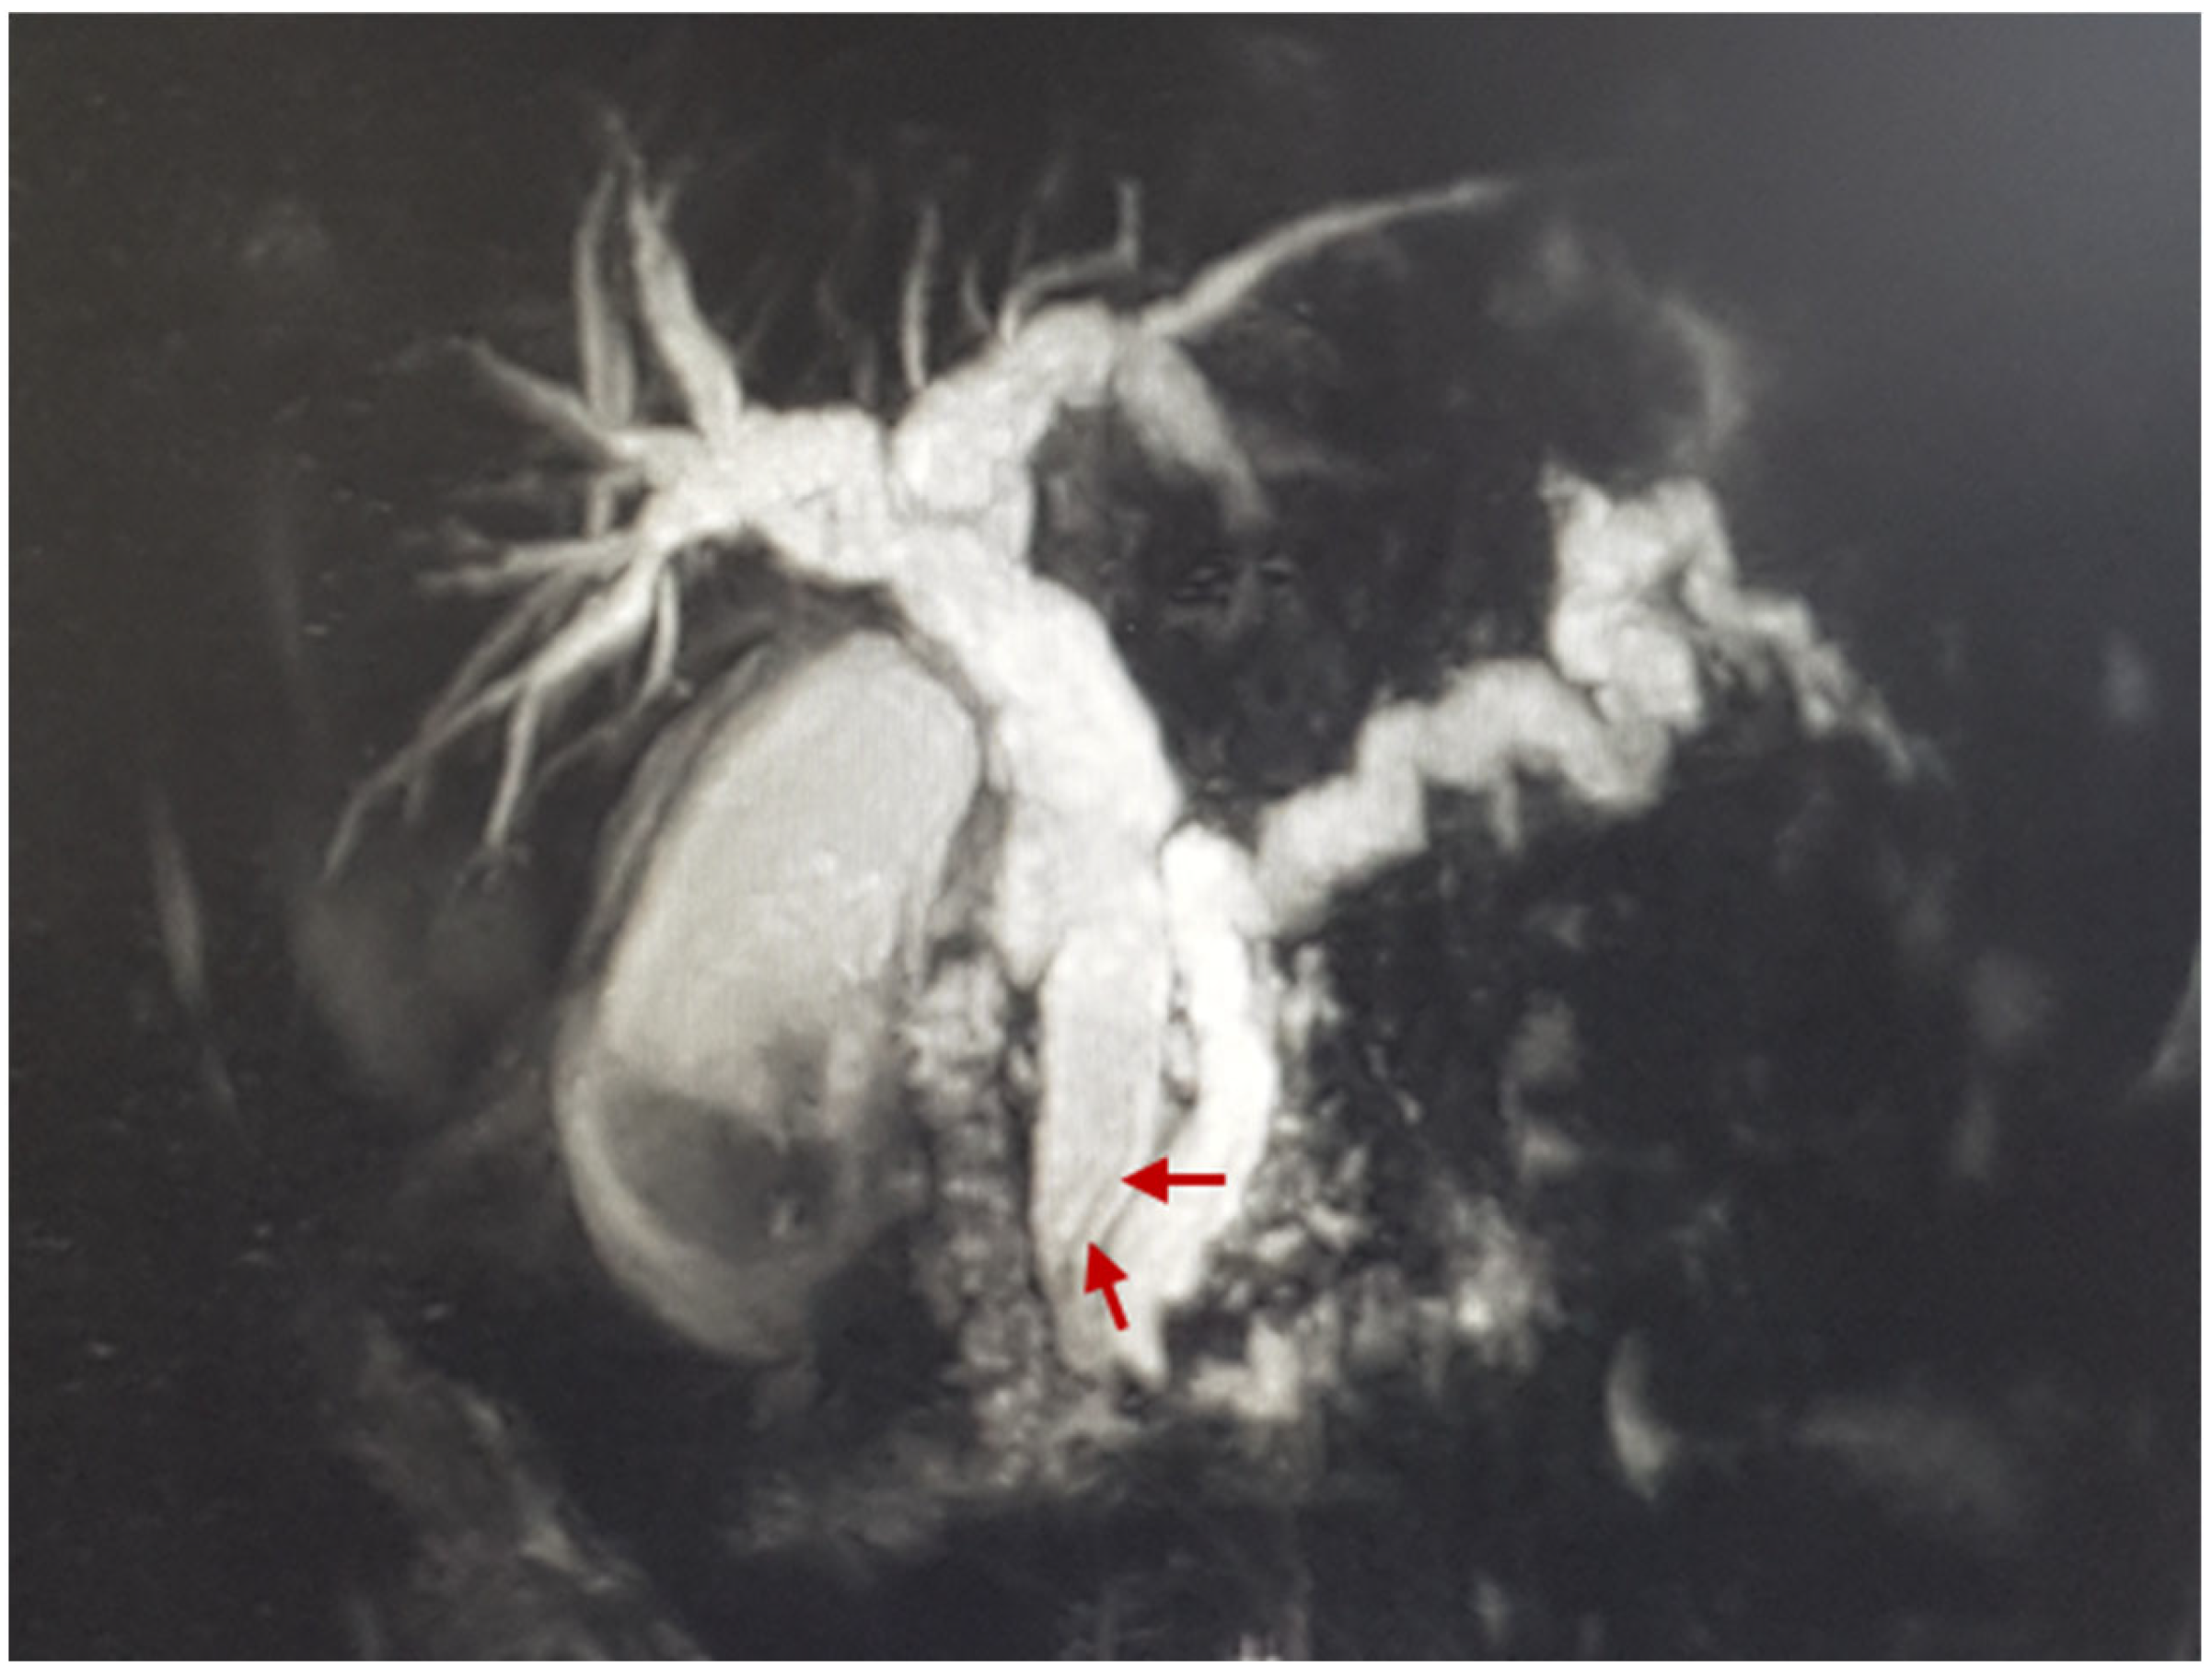

Magnetic resonance cholangiopancreatography (MRCP) was performed. The test demonstrated the normal size and structure of the patient’s liver, with dilated hepatic and biliary ducts: the right hepatic duct (RHD) was ~0.9 cm in diameter, left hepatic duct (LHD) was ~1.0 cm, sectoral ducts were up to ~0.7 cm, and peripheral ducts were ~0.2 cm in diameter. The common hepatic duct (CHD) and common bile duct (CBD) were up to ~1.1 cm and ~1.2 cm in width, respectively, and filled with a cloudy fluid. CBD gradually narrowed up to a size of ~0.65 cm; at hiatus, CBD joined with the dilated common pancreatic duct, which demonstrated a visible filling defect measuring ~0.5 cm by 0.3 cm in the lumen. The gallbladder was enlarged and demonstrated many uneven, polycyclically contoured filling defects with a cloudy layer. The pancreas was homogenous, the pancreatic duct was curved along its entire length and enlarged to ~0.7 cm in size, and the secondary ducts were dilated (Figure 2).

Figure 2. MRCP: Shadow of an A. lumbricoides parasite in CBD (red arrow).